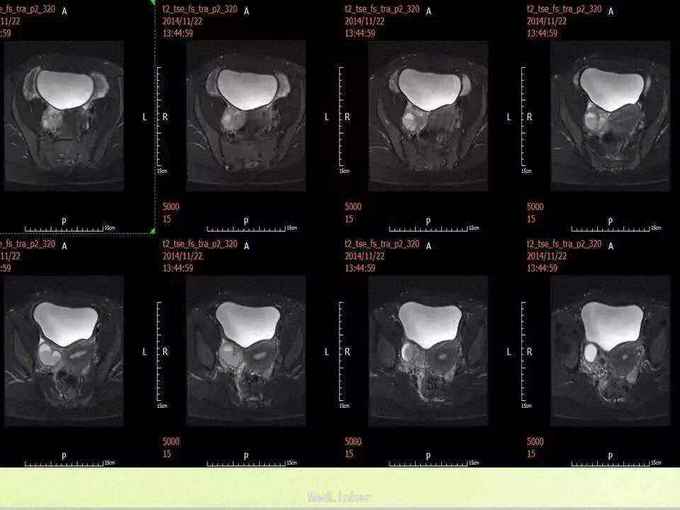

神清,精神可,浅表淋巴结未触及明显肿大,皮肤巩膜无黄染,腹壁静脉无曲张。腹平软,中上腹局部轻压痛,无反跳痛,未及腹肌紧张,肝、脾肋下未及,Murphy征(-),双肾区、脾区无叩击痛。移动性浊音阴性,叩诊鼓音,肠鸣音4次/分。 腹部MR:双侧附件区见多发类圆形长短T1等长T2混杂信号, FS-T2WI呈高信号,大者位于右侧,范围约4.7×3.2×5.9cm,注入GD-DTPA后呈明显不均质强化,其内见无强化区。盆腔内未见明显肿大淋巴结。盆腔内见少量长T2液性信号。诊断:双附件区异常信号,符合肿瘤MR表现,囊腺瘤可能性大。

初步诊断:双侧卵巢囊腺瘤?是否需行手术治疗?本例的情况需要考虑哪些疾病?